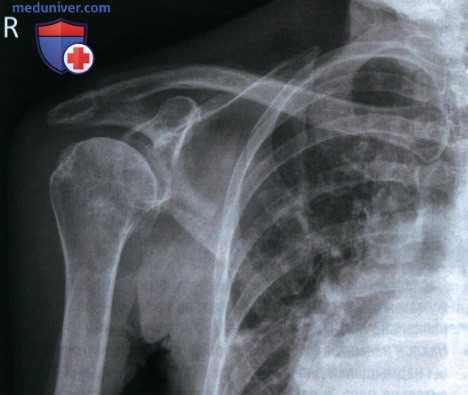

РИСУНОК 1 Рентгенограмма лопатки в ПЗ проекции: правильное положение.

• Передний и задний края суставной впадины лопатки почти накладываются друг на друга

• Грудная полость накладывается на позвоночный край лопатки, а не на ее латеральный край

• Отсутствует наложение ключицы на верхний угол лопатки

• Диафиз плечевой кости отведен на 90° (рис. 3 и 4)

• Отсутствует продольное проекционное укорочение лопатки

• Верхний угол лопатки визуализируется чуть ниже ключицы (на 0,6 см)

• Середина тела лопатки находится в центре экспозиционного поля

• В экспозиционное поле входит лопатка

• Структуры лопатки, накладывающиеся на грудную клетку, характеризуются приемлемым контрастным разрешением